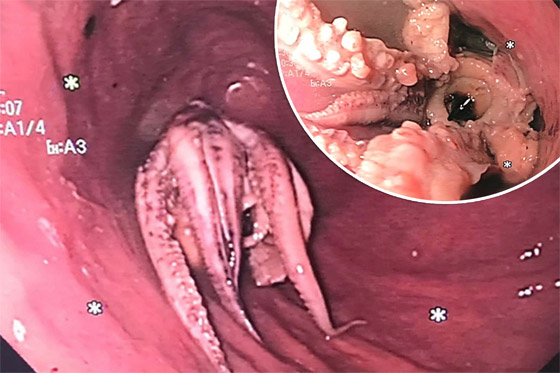

وشارك معهد الجمعية الأميركية للجهاز الهضمي (AGA) صورا مأخوذة من كاميرا المنظار الداخلي، وتُظهر المخلوق ذي المجسات الثمانية العالق في مريء الرجل. في البداية، جرب الأطباء "تقنية الدفع" ولكن سرعان ما اتضح أن الأخطبوط لن ينزل للأسفل، والضغط المفرط قد يؤدي إلى تمزق المريء. لذلك كان عليهم استخدام الملقط للإمساك بالمخلوق البحري وسحبه خارج المريء. وليس من الواضح لماذا ابتلع الرجل الأخطبوط كله، ولكن لحسن الحظ تعافى جيدا وخرج من المستشفى بعد يومين.

الأطباء ينقذون رجلا علق أخطبوط في حلقه! صورة رقم 2